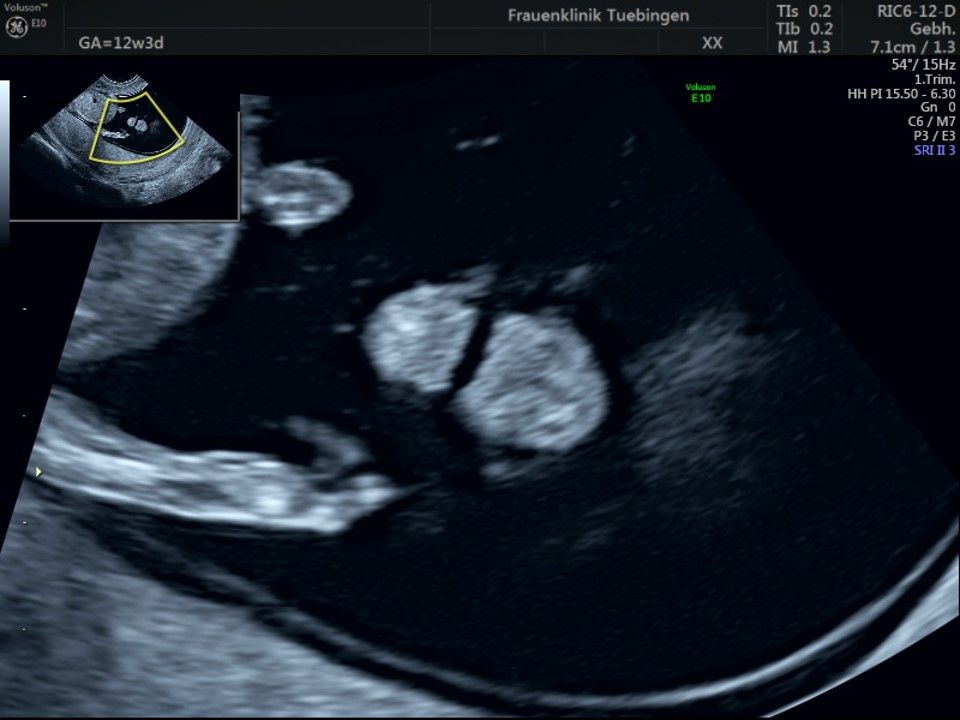

Herz

Das Ergebnis der Ultraschalluntersuchung ist wegweisend. Dabei wird der Fet vermessen, die Organe werden untersucht und die sonographischen Marker zur Risikoberechnung für Chromosomenstörungen werden beurteilt. Das sind: die Nackentransparenzdicke, Nasenbein sowie der Blutfluss in der rechten Herzhälfte und im Ductus venosus, einem Gefäß in der Leber des Feten.